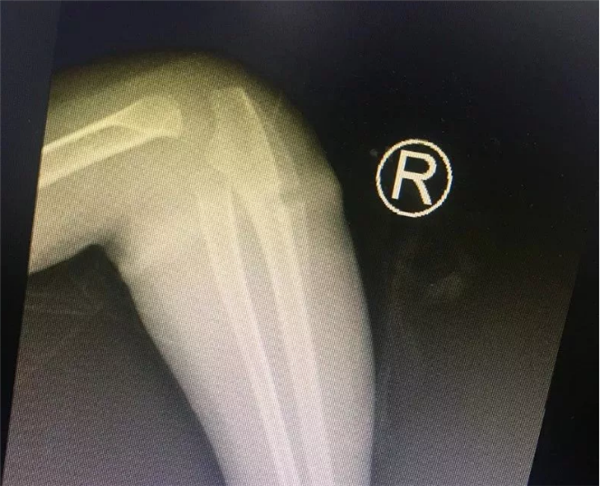

几天前,困扰安徽临泉乐乐一家人半年之久的手臂“圆环”事件终于真相大白了。难以想象的是一根很普通的橡皮筋竟然偷偷“长”进孩子的肉里!最终,浙大儿院湖滨院区骨科叶文松副主任在孩子的手臂中找出橡皮筋,解决了孩子手臂肿胀的痛苦。

4岁的乐乐长期跟着爷爷奶奶生活,不知从什么时候开始,右侧手臂莫名其妙长了一圈“圆环”。最初家里人没有在意这个“圆环”,哪知道乐乐的右前臂一天比一天更红肿。2018年过年后,乐乐手臂严重肿胀,疼痛,而且手指活动受限。看到孩子右前臂比左前臂足足肿大了一圈,这时乐乐的家人才担心起来。

随后,乐乐的父母带着女儿在安徽多家医院就诊,但乐乐的病太“怪”了,多家医院都没能查出乐乐手臂肿胀的真正原因。有的医生考虑是皮炎,有的考虑感染……可对症处理后,乐乐的手臂根本不见好转。不久前,他们专程带着乐乐来到了浙江大学附属儿童医院,找到了叶文松副主任医师。

叶主任看了乐乐的手臂,告诉孩子的家长,“圆环”很可能是橡皮筋导致的。虽然乐乐父母不大相信,还是听从叶主任的建议,让乐乐入院了。没多久,入院后B超检查结果出来了,也证实了叶主任的诊断是正确的。

有了明确的诊断,骨科各位医生开始为乐乐手术。这个手术并不难,无影灯下,历经半小时就将“圆环”擒拿归案,把长在肉里的环形橡皮筋取了出来,彻底解决了乐乐的病痛。